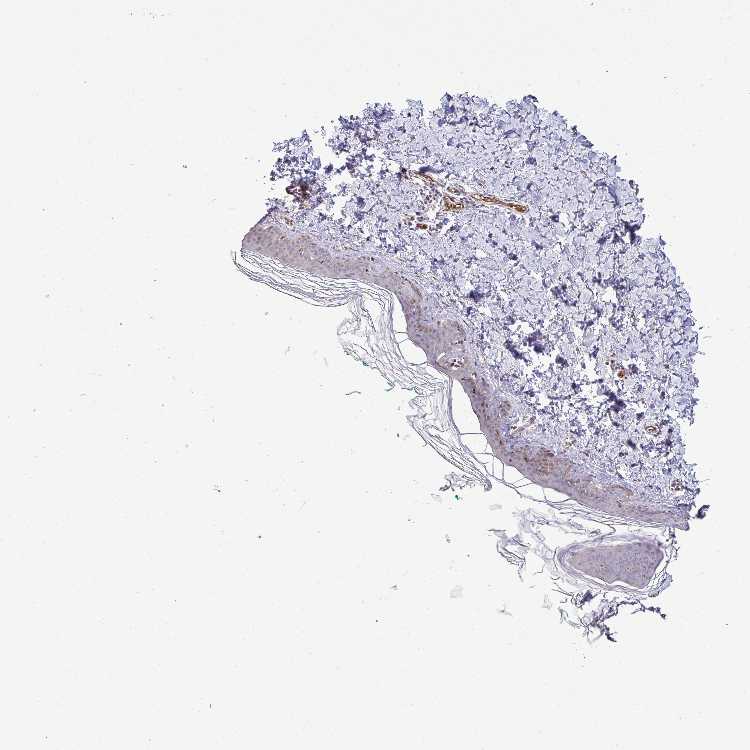

SKIN 1 - Antibody stainingi

Antibody staining in the annotated cell types in the current human tissue is reported as not detected, low, medium, or high, based on conventional immunohistochemistry profiling in selected tissues. This score is based on the combination of the staining intensity and fraction of stained cells.

Each image is clickable and will lead to virtual microscopy that enables deeper exploration of all samples and also displays staining intensity scores, fraction scores and subcellular localization as well as patient and tissue information for each sample.

Antibody HPA055353

Langerhans Medium

Fibroblasts Not detected

Keratinocytes Not detected

Melanocytes Not detected

SKIN 2 - Antibody stainingi

Epidermal cells Low